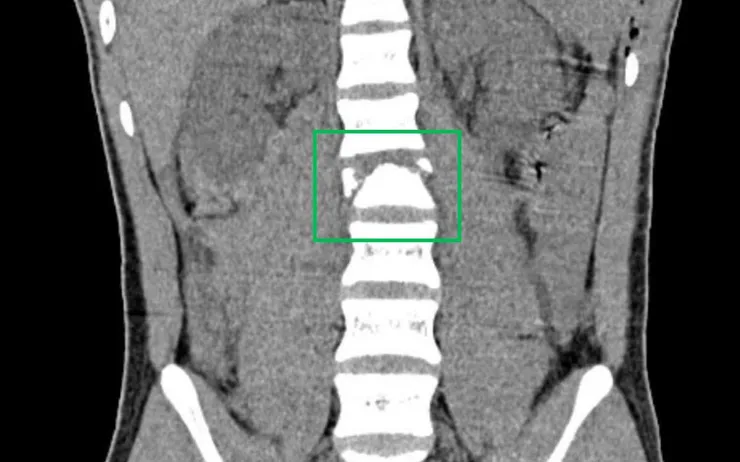

Theo người nhà, em bị trượt ngã khi đang đi xe máy và xuất hiện đau hai chân. Kết quả chẩn đoán tại bệnh viện địa phương cho thấy tủy sống bị đứt, xương sống gãy vỡ phức tạp, nên bệnh nhi được chuyển khẩn vào Bệnh viện Nhi đồng 2.

Ekip phẫu thuật đã nhanh chóng đặt dụng cụ cố định cột sống, giúp giảm đau và ngăn biến chứng loét do nằm lâu.

Dù khả năng phục hồi vận động rất thấp, các bác sĩ vẫn nỗ lực tối đa để bảo tồn chức năng, giúp bệnh nhi có cơ hội cải thiện chất lượng sống.